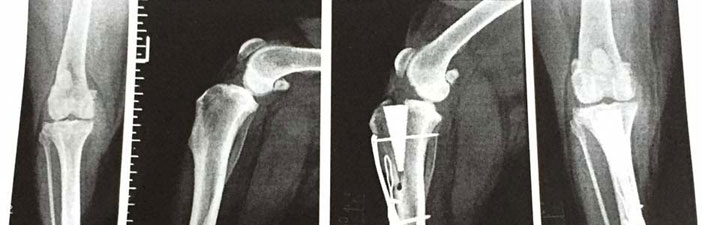

A Grade 3 Sprain being a complete rupture will require surgery as will a Grade 4.

Rehabilitation times after surgery is around 3 months or 6 months for giant dogs.

- Post surgery rehabilitation after TPLO/TTA